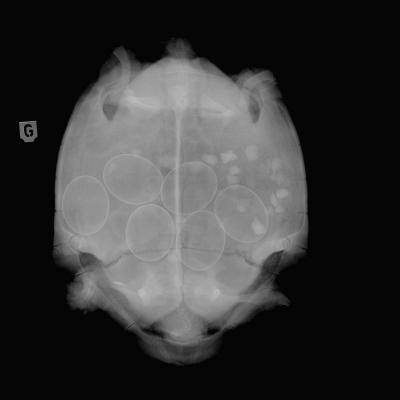

Tortue

Oeufs de Tortue